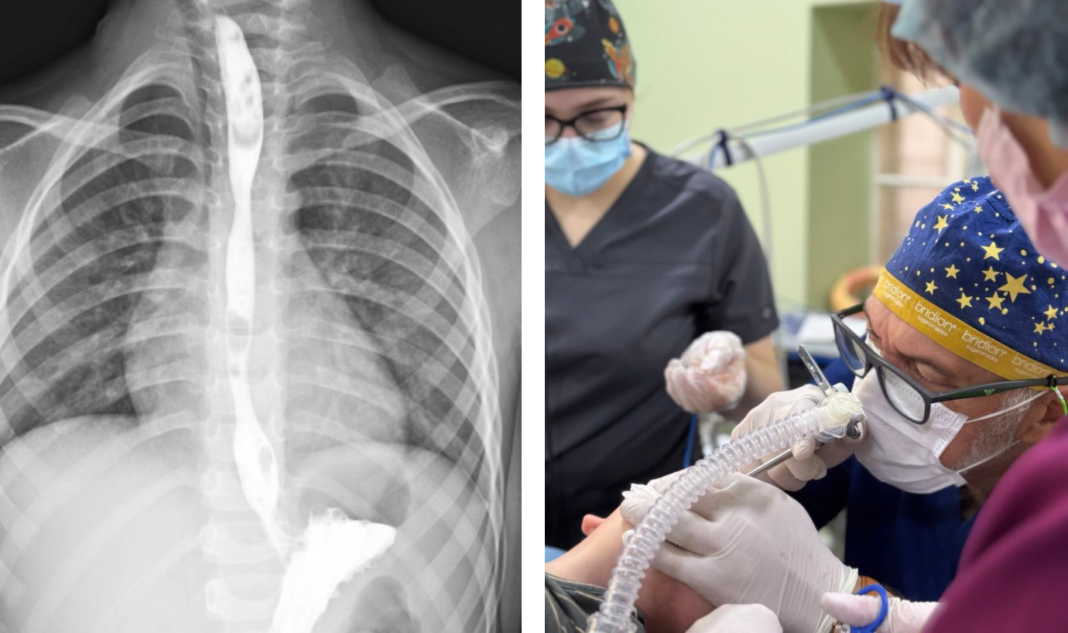

Хімічна речовина спричинила тяжкий опік стравоходу. На момент госпіталізації стан малюка був вкрай важким: він не міг самостійно приймати їжу, страждав від сильного болю, слинотечі та блювання. Дитину негайно доправили до відділення інтенсивної терапії.

Згодом у хлопчика сформувався критичний стеноз стравоходу — суттєве звуження просвіту, яке повністю унеможливлювало прийом їжі через рот.

Після консультацій мультидисциплінарної команди медики ухвалили рішення провести серію балонних дилатацій — малоінвазивних ендоскопічних процедур, під час яких звужену ділянку поступово розширюють спеціальним балоном без хірургічних розрізів.

“Це була складна, тривала та поетапна робота, але завдяки злагодженим діям команди нам вдалося уникнути великої травматичної операції”, — зазначив керівник Клініки торакальної хірургії та реконструктивної урології у дітей лікарні “Охматдит” Олег Ленів.

До лікування долучилися торакальні хірурги, анестезіологи, медсестри, фахівці інтенсивної терапії та рентгенолог Зеновія Жидяк. Зокрема, у команді працювали торакальний хірург Роман Ковальський та анестезіолог Віра Приймакова разом із колегами відділення.